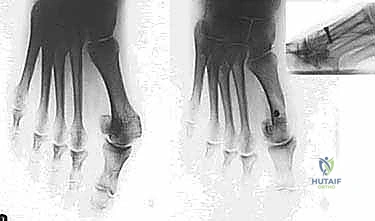

- التصوير بالأشعة السينية الدقيقة (Weight-Bearing X-Rays): وهي خطوة حاسمة. يجب أن تؤخذ الأشعة والمريض واقف (يحمل وزنه على قدمه) لإظهار الحجم الحقيقي للتشوه.

- القياسات الهندسية لزوايا القدم: يقوم الدكتور هطيف بقياس زوايا محددة لتحديد نوع الجراحة، أهمها:

- HVA (Hallux Valgus Angle): زاوية انحراف الإبهام (الطبيعي أقل من 15 درجة).

- IMA (Intermetatarsal Angle): الزاوية بين العظمة المشطية الأولى والثانية (الطبيعي أقل من 9 درجات).

- DMAA (Distal Metatarsal Articular Angle): زاوية سطح المفصل، وهي الزاوية الأهم التي تحدد الحاجة لتقنية "ش